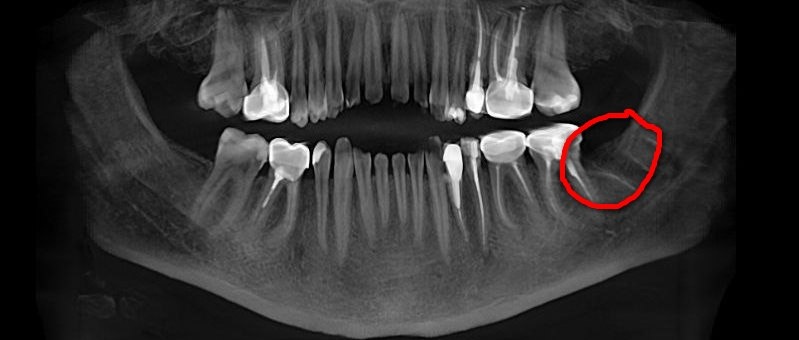

📍 Ещё один клинический случай из практики Дениса Сергеевича: зуб 28 (на фото верхний справа) затруднял проведение полноценного лечения зуба 27 из-за тесного прилегания к нему. В связи с этим было принято решение об удалении данной «восьмёрки». У остальных зубов мудрости были выявлены повторные признаки перикоронита, и с учётом предстоящего ортопедического лечения они были планово удалены.